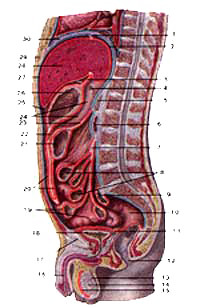

Топография внутренних органов и брюшины в брюшной полости мужчины

Срединный сагиттальный разрез.

1-венечная связка печени;

2-верхнее сальниковое углубление;

3-печеночно-желудочная связка;

4-зонд в сальниковом отверстии;

5-поджелудочная железа;

6-двенадцатиперстная кишка;

7-корень брыжейки тонкой кишки;

8-тонкая кишка;

9-сигмовидная кишка;

10-прямая кишка;

11-прямокишечно-пузырное углубление;

12-задний проход;

13-придаток яичка;

14-яичко;

15-полость влагалищной оболочки яичка (серозной оболочки яичка);

16-мочеиспускательный канал;

17-лобковый симфиз;

18-мочевой пузырь;

19-петли тонкой кишки;

20-большой сальник;

21-поперечная ободочная кишка;

22-нижнее сальниковое углубление;

23-брыжейка поперечной ободочной кишки;

24-сальниковая сумка;

25-преджелудочная сумка;

26-желудок;

27-печеночная сумка;

28-печень;

29-мечевидный отросток грудины;

30-диафрагма.